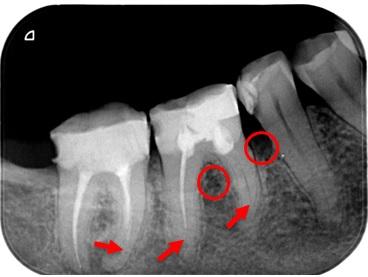

Nedostatočne zaplnené koreňové kanáliky (červené šípky), kostný defekt vplyvom zápalu (červené krúžky)

Úspešne vykonaná reendodoncia, odstránenie starej nevyhovujúcej koreňovej výplne, opätovné zaplnenie koreňových kanálikov a výplň korunkovej časti zuba.